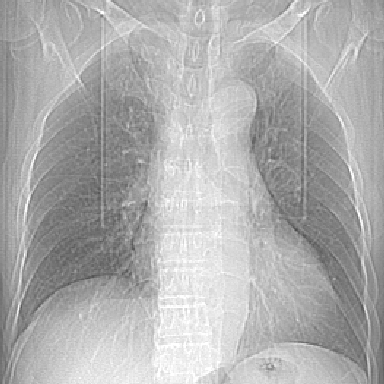

标题: CT8275:M 77 反复咳嗽咳痰10多年,慢性支气管炎请分析 [打印本页]

标题: CT8275:M 77 反复咳嗽咳痰10多年,慢性支气管炎请分析

m 77 反复咳嗽咳痰10多年,再发加重4天